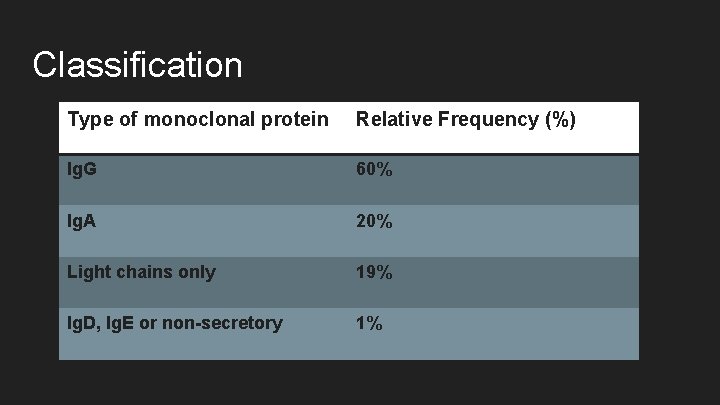

Classification Type of monoclonal protein Relative Frequency (%) Ig. G 60% Ig. A 20% Light chains only 19% Ig. D, Ig. E or non-secretory 1%